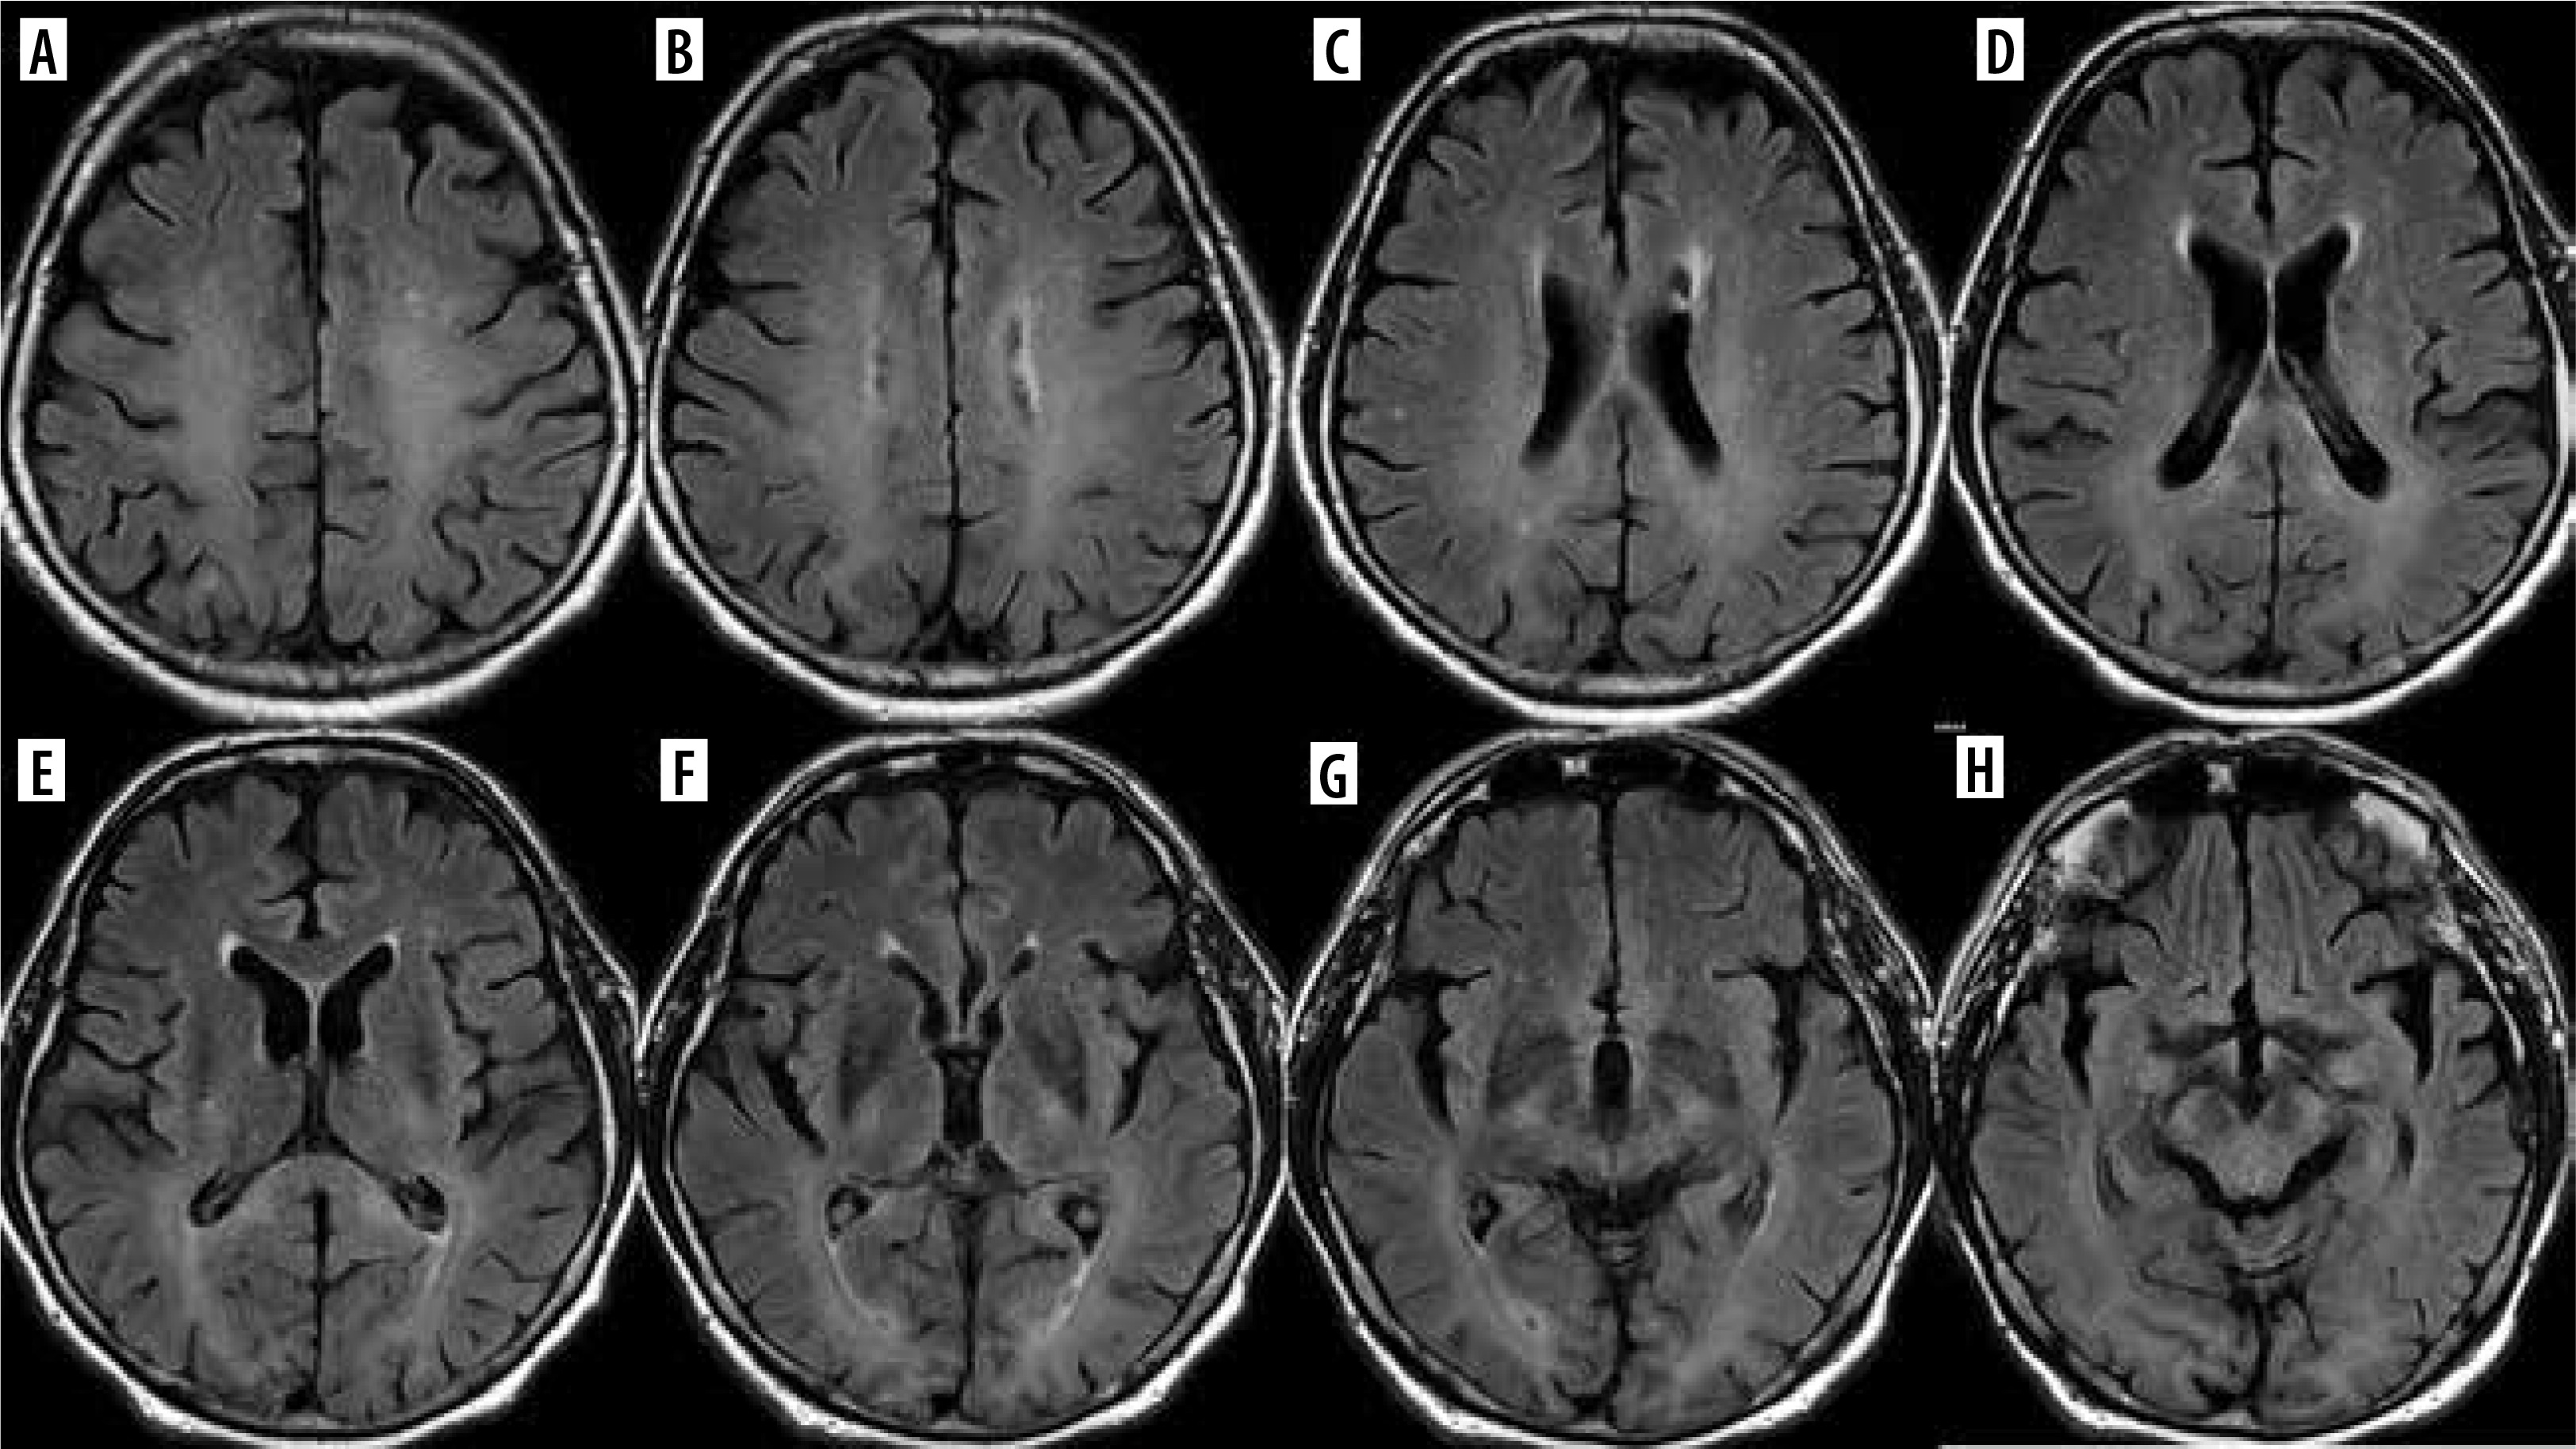

Immunotherapy with CAR-T (chimeric antigen receptor T-cell) is used for the treatment of acute lymphoblastic leukemia and lymphomas and can result in remarkable clinical outcomes, but is associated with potentially fatal neurotoxicity: immune effector cell-associated neurotoxicity syndrome (ICANS). This is a clinical diagnosis with heterogeneous neuroimaging findings which can be grouped anatomically (involvement of the white matter, gray matter, brainstem, or leptomeninges) or pathologically (ischemic or hemorrhagic lesions, or cerebral edema) [25] (Figure 8).

Figure 8

Presumed ICANS in a 45-year-old woman with primary mediastinal lymphoma treated with CAR-T. After 3 weeks disturbance of consciousness, the patient was unconscious on the day of MRI. Discrete T2 (D) and FLAIR hyperintensities (A-C) in the frontal and parietal white matter, and in the corpus callosum (arrows). No diffusion restriction (DWI – E, G, corresponding ADC maps – F, H), no contrast enhancement. After about a month, the symptoms withdrew